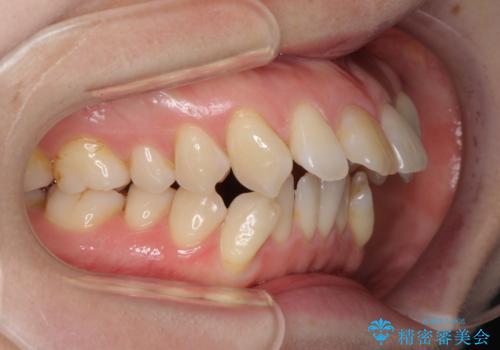

- 上の前歯の飛び出した感じを改善したいとのことで来院された患者様です。

上顎左右第一小臼歯2本、下顎左右第二小臼歯2本を抜歯し、ワイヤー装置にて口元を引っ込めるよう矯正治療を行うこととしました。

上下の前歯に隙間が空くほど上顎前歯が前に飛び出していましたが、抜歯矯正により上下前歯がぴったりと付くほど口元を引っ込めることができました。